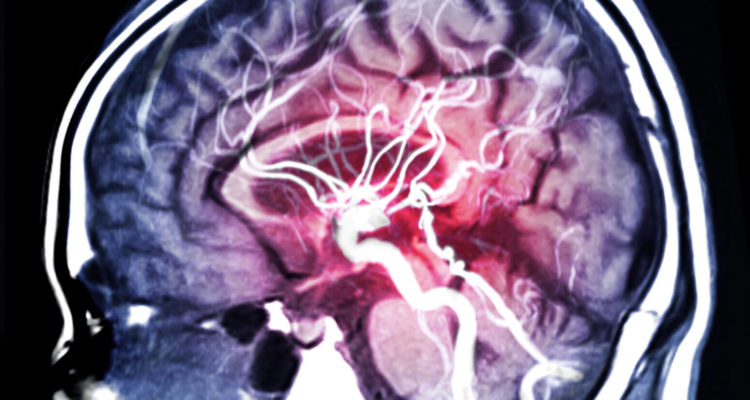

Лікарі знайшли спосіб знизити ризик інсульту та ішемічної хвороби

Серцево-судинні захворювання вважаються однією з найчастіших причин передчасної смерті в світі. За деякими оцінками, від них щорічно помирає близько 18 млн осіб.

Нове дослідження лікарів з Гарвардського університету вказало на те, чому нездорове харчування підвищує ризик розвитку небезпечних серцево-судинних захворювань. Цього разу мова йде не про зайвий холестерин, а про інші небезпечні явища в організмі. За даними лікарів, дієта з високим вмістом червоного і переробленого м’яса, солодких напоїв і білого хліба сприяє запаленням в організмі і збільшує подальший ризик серцевих захворювань та інсульту.

Дослідники проаналізували дані більш ніж 210 тис. учасників довгострокових медичних спостережень. З них у 15,8 тис. спостерігалися серцево-судинні захворювання, у тому числі майже 9,8 тис. випадків ішемічної хвороби і майже 6,2 тис. випадків інсульту. Виявилося, що більш високий запальний потенціал в дієті був пов’язаний з підвищеним ризиком серцевих захворювань, ішемічної хвороби серця та інсульту. Ці співвідношення були постійними для різних груп і статей і залишалися значними після подальших Коригувань для інших показників якості харчування.

Грунтуючись на результатах дослідження, американські лікарі рекомендують включати в раціон продукти з більш високим рівнем антиоксидантів і клітковини, які допомагають боротися із запаленням. До них відносяться такі продукти, як зелені листові овочі (наприклад, капуста і шпинат), жовті овочі (наприклад, боби, морква і гарбуз), а також кава, чай, вино і цільнозернові продукти.